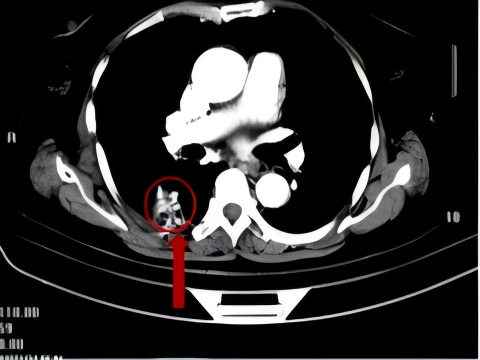

2011年,一名70岁患者因出现咳嗽、咳痰带血等症状就诊于我院呼吸门诊,在完善CT等相关检查后,患者被诊断为右上腺癌(多原发),在充分的与患者及家属进行沟通后,明确表示不接受外科手术,科室为患者制定并实施了CT引导下经皮肺穿刺射频消融+碘125粒子植入放疗+化疗的治疗方案。

术 前

术 后

患者分别在治疗4月和1年后复查胸部CT显示病灶稳定,病情得到进一步控制。